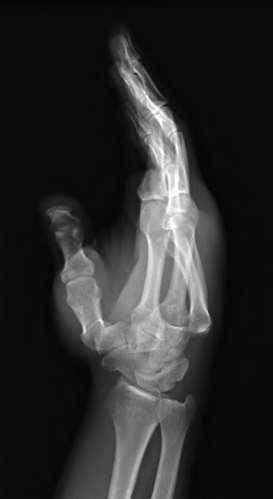

A 20-year-old park ranger trips and falls onto his right wrist with the wrist in extension and pronation. The local urgent care orders both radiographs and a CT, which you review and determine to be normal. The patient complains of ulnar-sided wrist pain. On exam, his tenderness is localized to the fovea. Ulnar deviation also causes him pain. There is no snapping sensation with wrist supination, flexion, and ulnar deviation. He otherwise has 5/5 strength to his first dorsal interosseous muscle with 4mm static two-point discrimination on the ulnar side of the 4th digit. Which of the following injuries is most likely responsible for his symptoms and exam?

volar tenderness along the flexor sheath